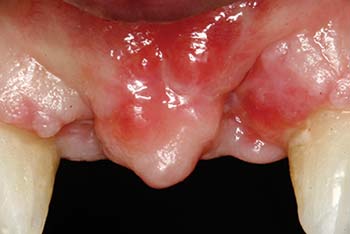

MinerOss Cancellous defect

maxillary defect

MinerOss Cancellous graft

MinerOss Cancellous case images courtesy of Bach Le, DDS, MD, FICD, FACD